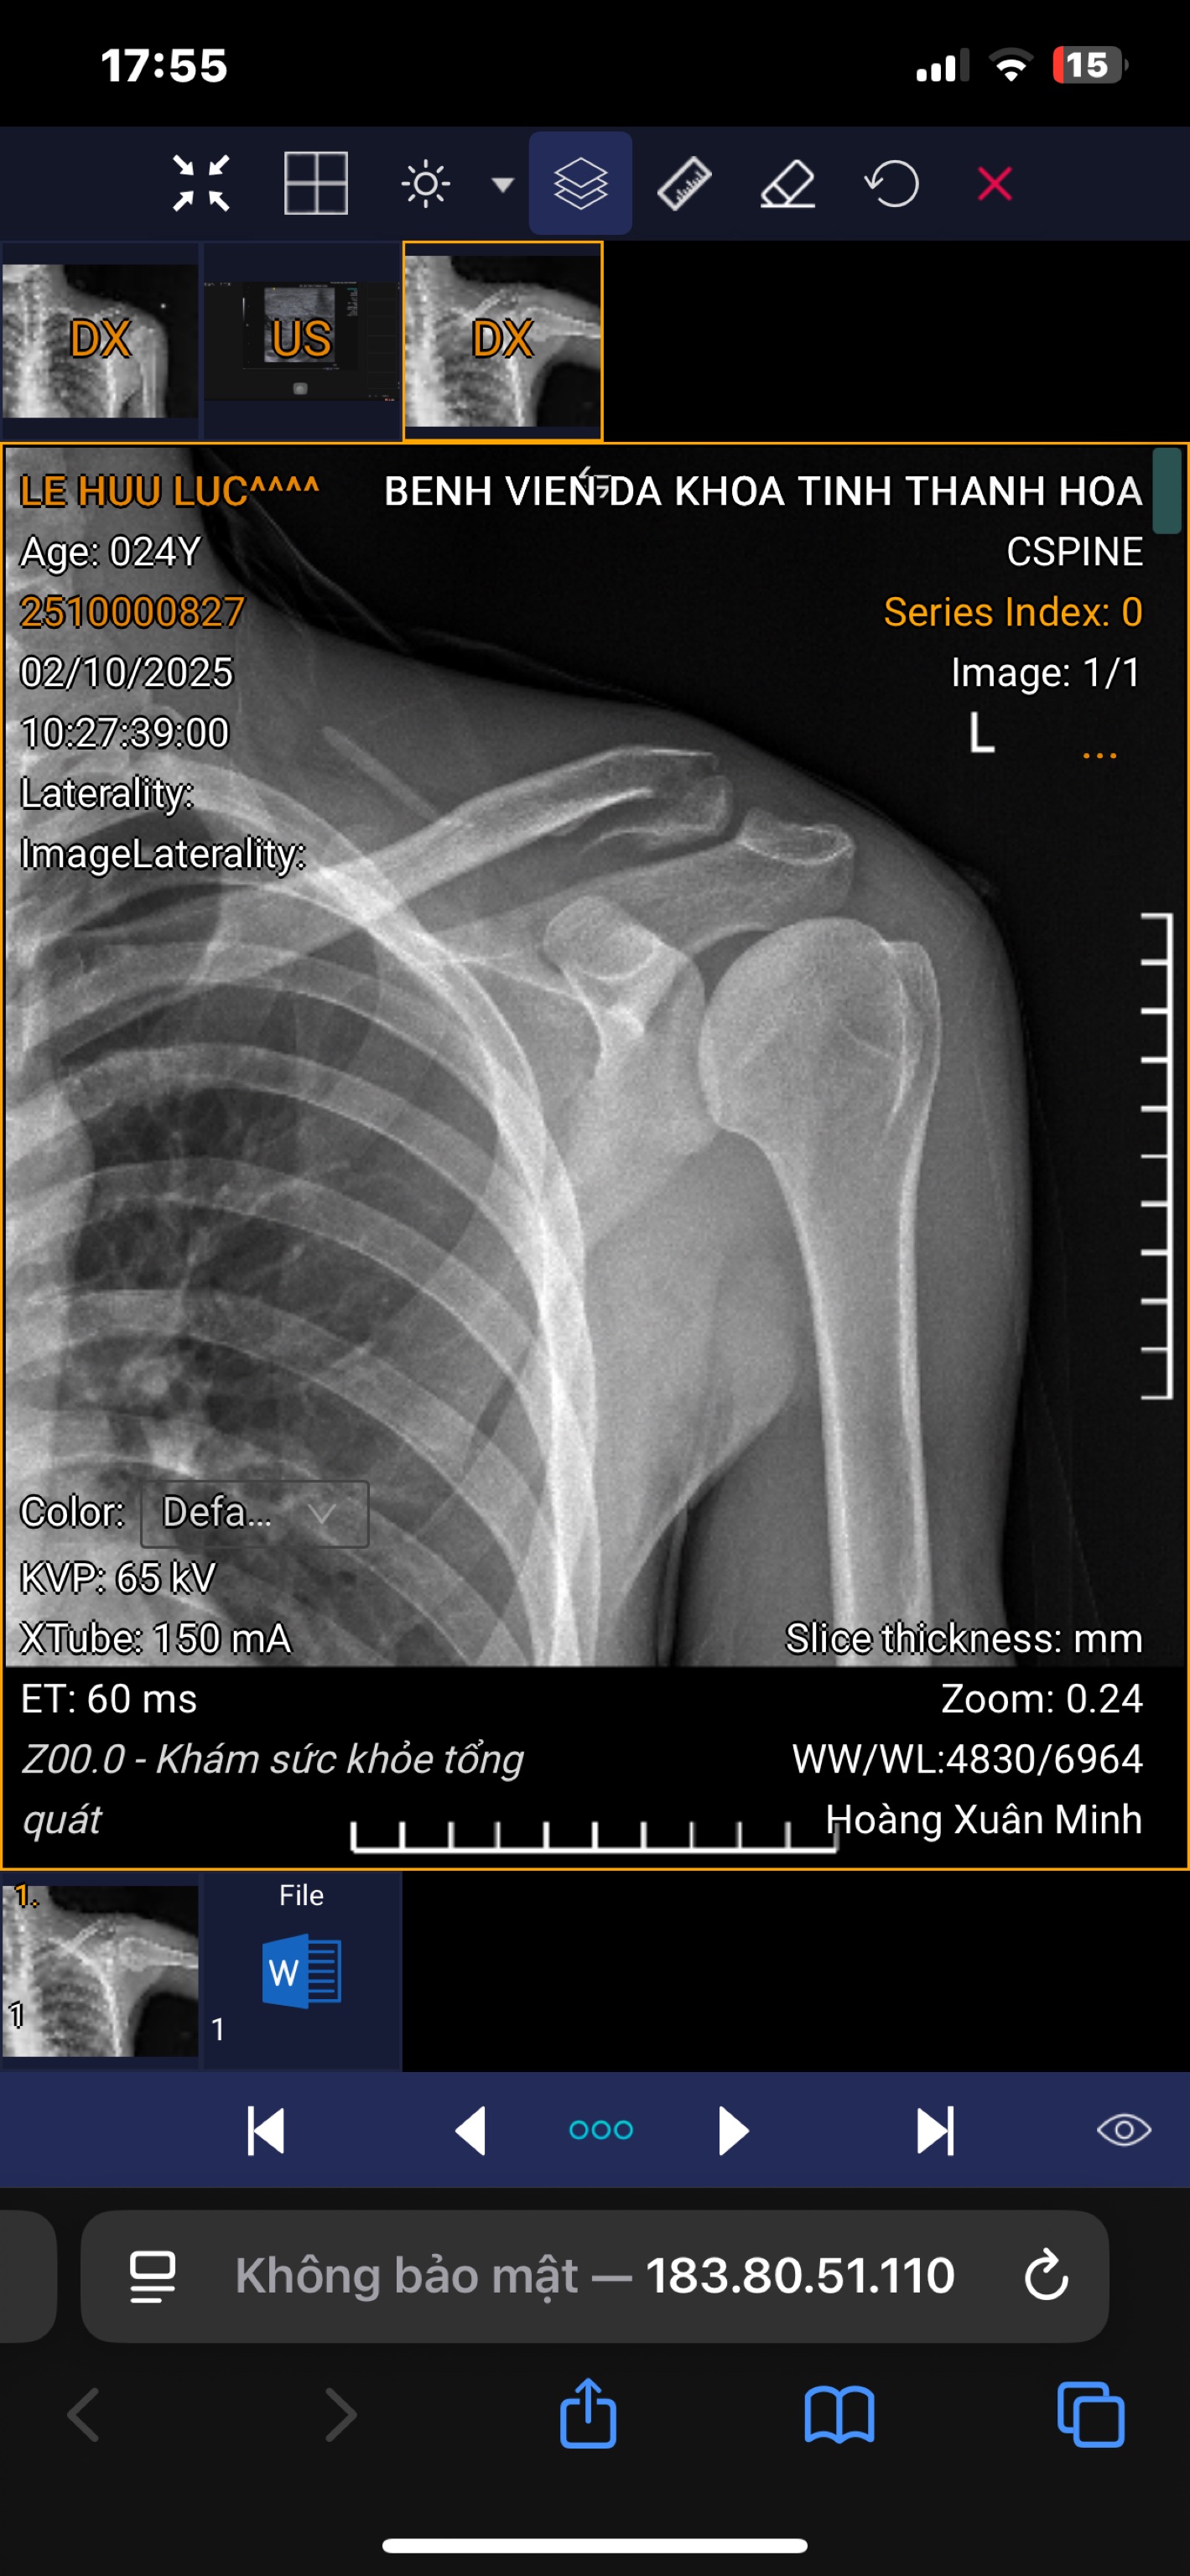

E muốn hỏi e mỗ gãy đầu ngoài xương đòn trái nhưng bản thân e chỉ muốn nằm viện 2-3 ngày được không ạ

Dạ ảnh của e đây ạ do công việc e đang có ý định thời gian trk mắt không mổ bác sĩ xem có nên không ạ